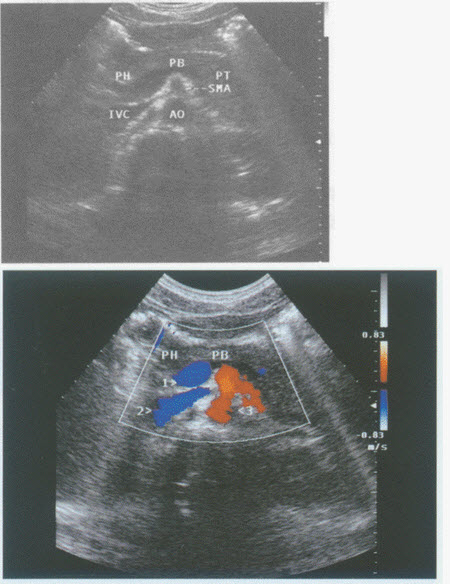

请回答下图及彩图声像图中1、2、3所指部位的解剖名称()

A . .1-脾静脉、2-下腔静脉、3-腹主动脉

B . 1-门静脉、2-下腔静脉、3-腹主动脉

C . 1-脾静脉、2-右肾静脉、3-腹主动脉

D . 1-脾静脉、2-下腔静脉、3-肠系膜上动脉